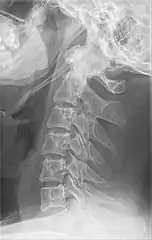

![]() | |

| Anteroposterior and lateral radiographs of cervical spine showing ossification of the stylohyoid ligament on both sides | |

Radiograph, lateral view showing elongated stylohyoid process and stylohyoid ligament ossification

Radiograph, lateral view showing joint-like formation in ossified stylohyoid ligament